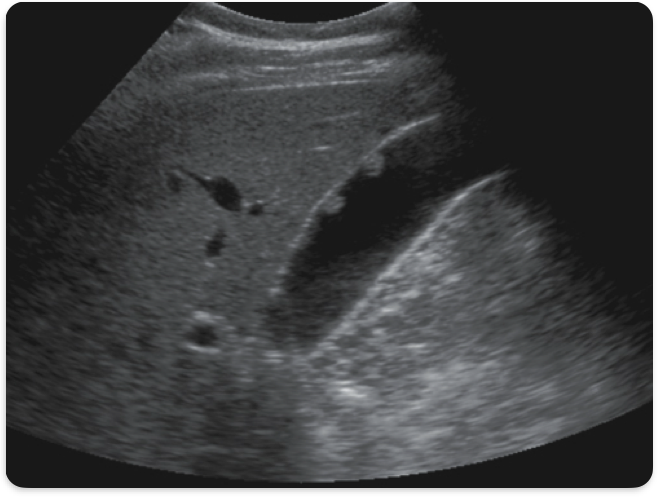

WES sign

GB completely filled w/ stones. Only anterior wall visualized

Cholelithiasis, gallstones